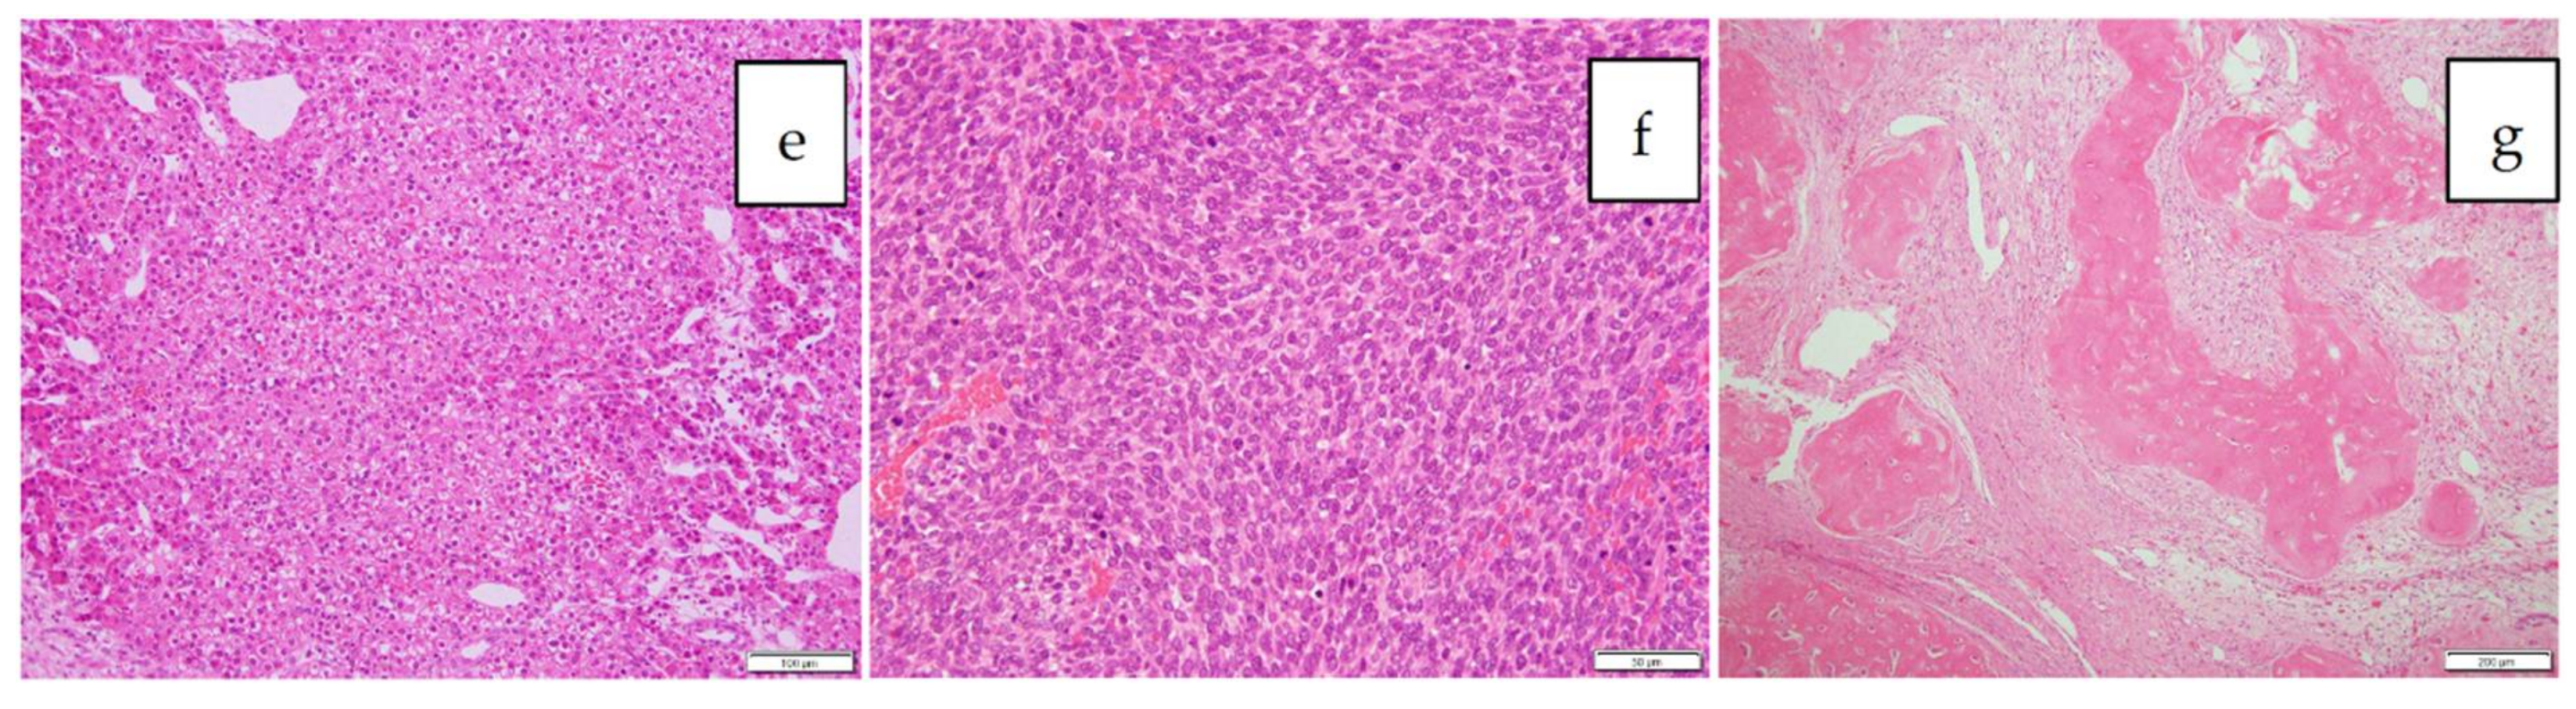

Since the number of subjects thus far has been small, no clear association has been noted between the fluorescence pattern and pathology. However, it is important to note that all patients with HB in our series underwent sessions of chemotherapy before resection, whereas patients with HCC usually do not. Therefore, all of the primary lesions subjected to the studies were evaluated post-chemotherapy, and a certain percentage of necrotic and fibrotic areas were observed macroscopically. Such areas generally appeared non-fluorescent and were therefore described as an uneven fluorescence pattern in vivo, as shown in Figure 1a,b and Figure 2a,b. Interestingly, HB with teratoid features also demonstrated uneven fluorescence both in vivo and ex vivo, with fluorescence being observed in only well-differentiated HB lesions, as shown in Figure 3a–g. In addition, we experienced cases of metastasectomy for HB in a transplanted liver graft, with multiple small lesions visualized as a diffuse pattern, as shown in Figure 4a–d [43].

Figure 3.

a–g: Mixed epithelial and mesenchymal type with teratoid features, post-chemotherapy. The formalin-fixed cross section of the liver is shown (a), and the tumor is encircled with a yellow-dotted line. The tumor is heterogeneous macroscopically, and fluorescence can be observed only in the small area marked with a white-dotted line (b: white-light mode, c: NIR mode, d: mapping mode). A histological analysis showed that while the fluorescent area corresponded to well-differentiated HB (e), the non-fluorescent area consisted of poorly differentiated HB (f) and an osteoid lesion (g). Scale bar: 100 µm.